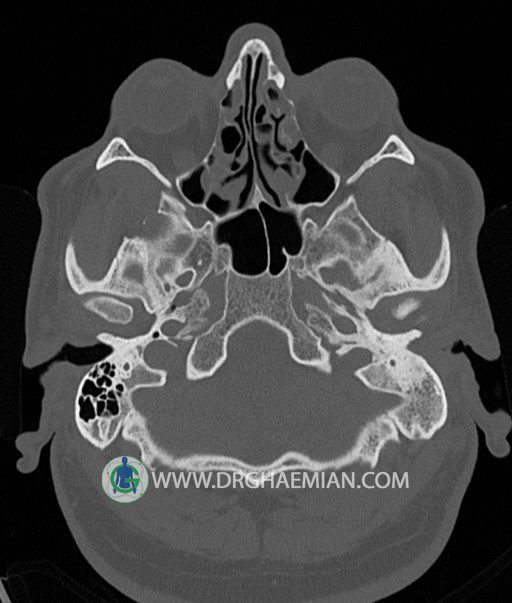

سی تی اسکن گوش داخلی به رادیولوژیست اجازه می دهد تا سطوح مختلف، یا اسلایس هایی از استخوان های که از جمجه به گوش می روند را از طریق امواج ایکس چرخشی مشاهده کند. در این کیس اودیت مدیا، ماستوئیدیت مزمن، اوتیت خارجی، انحراف سپتوم بینی، کونکا بولوزا و افزایش ضخامت سینوس ها مشاهده می شود.

در HRCT از استخوان تمپورال با مقاطع آگزيال ، ساژيتال و کرونال ظريف ( 0.6 mm ) :

– نماي کوکلهآي دو طرف با 2.5 دور گردش مجرا

– نماي cochlear aqueduct

– نماي semicircular canal خلفي ، لترال ، فوقاني و وستيبول

– استخوانچه هاي گوش داخلي شامل malleus ، incus و stapes (دنسيتي و رديف استخوانچه ها )

– نماي oval window و round window ، tympanic cavity ، attic و کانال گوش داخلي

– کانال عصب فاشيال و مسير ان از ناحيه کانال گوش داخلي ، geniculate ganglion تا محل خروج ان از stylomastoid foramen

– نماي tympanic membrane ، کانال ICA ، بولب جوگولار دو طرف

در حد طبيعي است .

– اپاسيتي گوش مياني چپ ناشي از وجود دانسيته نسج نرمي دراطراف استخوانچه ها همراه با اروژن اسکوتوم و

استخوانچه ها بدون جابجايي در رديف استخوانچه ها مشهود است که مطرح کننده اوتيت مديا همراه با نشانه

هاي مشکوک به کولستئاتوم مي باشد .

– اپاسيتي و اسکلروزيس ماستوئيد چپ نشانه ماستوئيديت مزمن

– اپاسيتي کانال گوش خارجي ناشي از دانسيتي نسج نرمي مطرح کننده external otitis

– انحراف سپتوم مياني بيني به راست

– کونکا بولوزا در کونکاي مياني چپ و

– افزايش ضخامت مخاطي در سينوس هاي اتموئيد و ماگزيلاري

اپاسيته